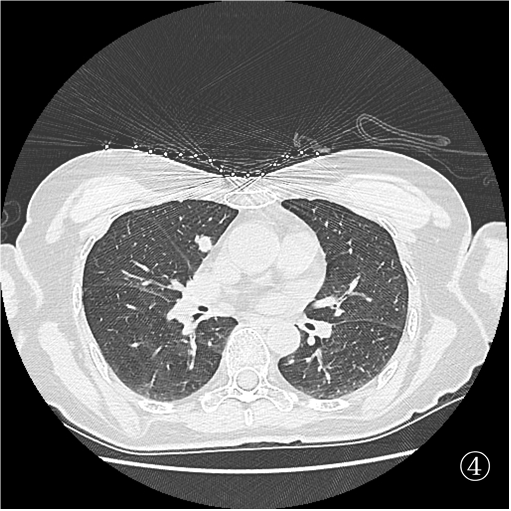

患者俯卧定位扫描(图③):由于胸腔及肺组织受压,左肺占位距离膈肌<1 cm,行穿刺活检必然损伤膈肌,可能造成严重并发症。于是决定经胸前穿刺右肺占位活检(图④),但由于病灶小于 1 cm 且邻近大血管,必须精准制导(图⑤)。穿刺后扫描局部少许出血,未见气胸(⑥)。

难点在于肺部占位较小(均<1 cm), 左肺占位穿刺相对安全,但由于俯卧位时病灶邻近膈肌,穿刺势必损伤膈肌。右肺占位穿刺风险较大(邻近重要大血管),故穿刺术前须精准定位,穿刺时须精准制导。另外,明确诊断后严格遵循循证医学证据科学治疗。